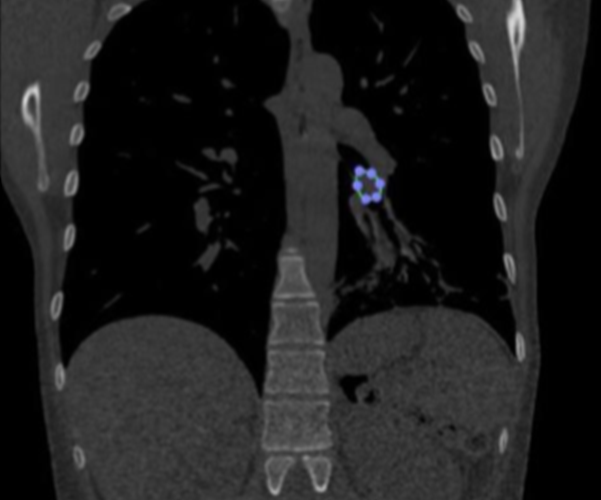

Mujer de 38 años, ex fumadora diagnosticada con tumor carcinoide bronquial localizado en el lóbulo inferior del pulmón izquierdo.

El primer plan quirúrgico, basado en las imágenes de Tomografía Computada, era una lobectomía inferior izquierda.

Luego de tener a disposición el modelo 3D de las vías aéreas de la paciente, el cirujano pudo localizar con precisión el tumor y notó que se encontraba por debajo de lo que creía. Además el modelo tridimensional permitió identificar fácilmente sus límites lo que permitía pensar en un nuevo plan para el tratamiento de la paciente.

De este modo, se cambió la estrategia quirúrgica y se realizó una resección bronquial segmentaria, que implicó extirpar únicamente el tumor salvando el lóbulo inferior de la paciente.

Seguidamente, se realizó una reanastomosis del árbol bronquial para reconstruir la vía aérea sin pérdida del parénquima pulmonar.